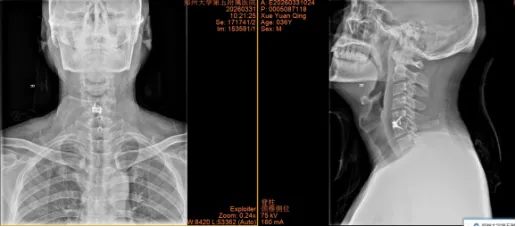

1.东莞市薛先生36岁

640_副本

640 (1)_副本